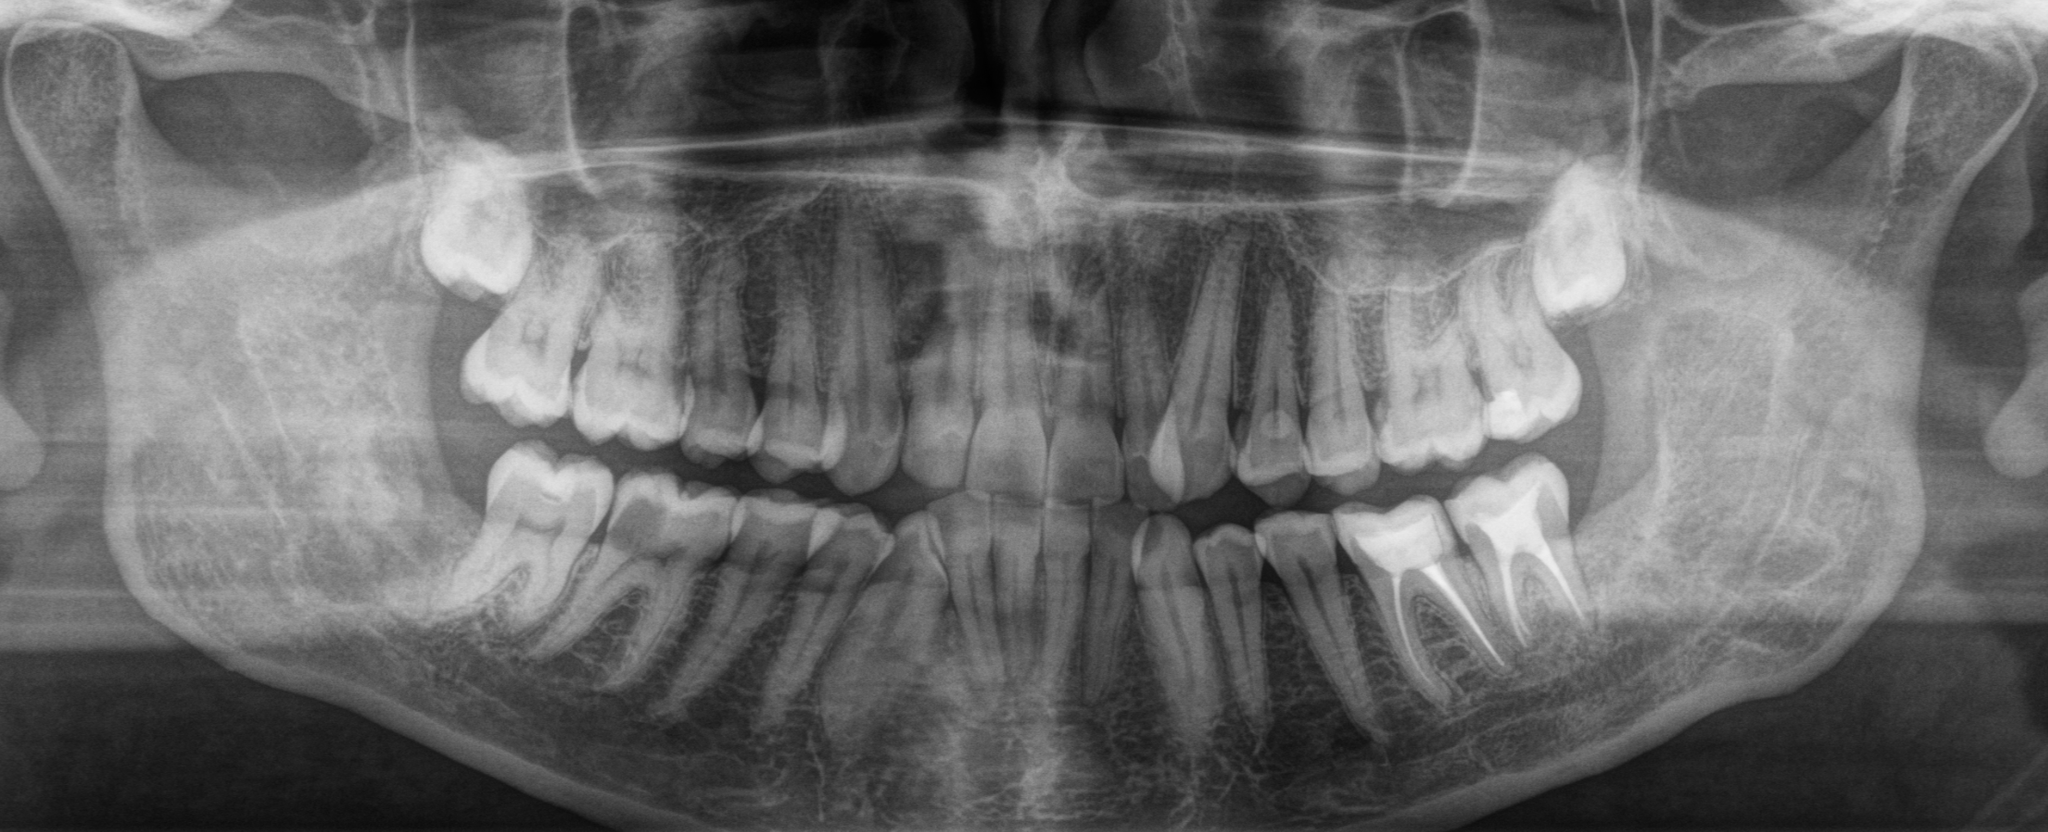

После удаления было проведено несколько осмотров, снятие швов – все как обычно. Через месяц – контрольный снимок.

Что мы видим? Темное пятно в области проведенной операции сохраняется, что нормально, потому как прошел всего месяц с момента удаления. Заживление проходит хорошо, каких-либо проблем в восстановлении не наблюдается. Не зря я отметил пунктиром область зуба мудрости с противоположной стороны, потому как там есть точно такая же фолликулярная киста, как и слева, но на начальных этапах своего роста.

Прошёл еще месяц. То самое «темное пятно» начинает постепенно «белеть», а ведь прошло всего 2 месяца со дня удаления.

Красными стрелками я отметил постепенное «появление» периодонтальной щели. Вон та черная полоска (пространство) между корнем зуба и костной тканью. Грубо говоря, там связка, которая выполняет опорно-удерживающую функцию, что позволяет зубу несколько амортизировать при жевании.

Следующий визит был запланирован через три месяца. Итак, новый снимок:

На данном снимке видно, что область удаления продолжает восстанавливаться, всё четче видны очертания нижнечелюстного канала, в котором проходит одноименный нерв.

Снимок спустя ещё три месяца:

А еще через три было проведено удаление 8-го зуба с правой стороны.

В общей сложности между удалениями прошел ровно год:

Ниже представлен последний на данный момент контрольный снимок, который был сделан в апреле 2021, спустя ровно полтора года после операции по удалению ретенированного зуба мудрости и фолликулярной кисты на нижней челюсти слева:

Нот бэд, как говорится. Всё четко, все восстановилось. Теперь задача пациента (в идеале) – делать контрольные снимки каждые полгода.